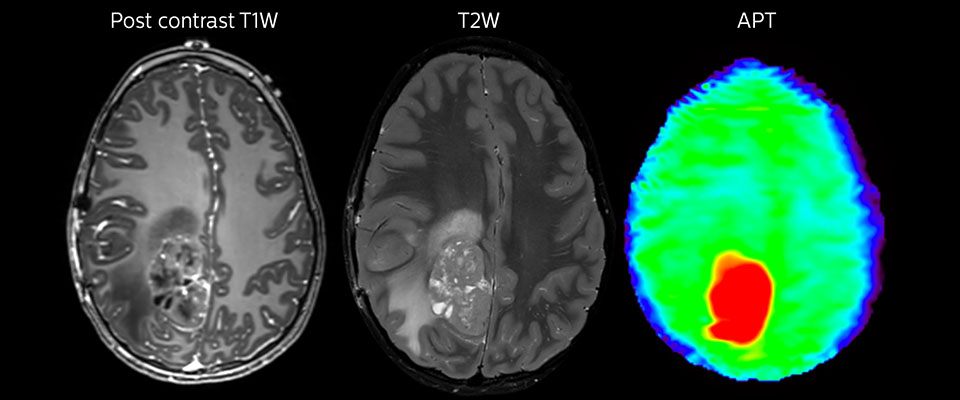

APT in post-surgery evaluation

Large metastatic brain lesion

This 10-year-old patient underwent Ewing’s sarcoma tumor resection 7 years ago, but was found to now have a large metastatic lesion in the brain. This lesion shows clearly increased APT signal.

MRI with APT post resection

Immediately post resection MRI was again performed. T2-weighted and postcontrast T1-weighted images are quite inconclusive for distinguishing residual tumor tissue from postoperative tissue changes. On the APT image some high signal is still seen, which would suggest residual tumor tissue.

Follow-up over time

In later follow-up scans the post-contrast T1-weighted images suggest recurrent tumor growth. So, it would be interesting to study the predictive value of APT in a large patient group.